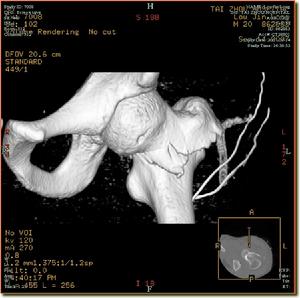

骨折後股骨矩的完整性未受到破壞,為穩定性骨折。股骨矩完整為不穩定型骨折。轉子進骨折有多種分類方法。參照Tronzo和Evans的分類分可將轉子間骨折分為五型:Ⅰ型,為單純轉子間骨折,骨折線由外上斜向下內,無移位。Ⅱ型,在Ⅰ型的基礎上,發生移位,合併小轉子撕脫骨折,但股骨矩完整。Ⅲ型,合併小轉子骨折,骨折累及股骨矩。有移位,常伴有準子間後部骨折。Ⅳ型伴有大、小轉子粉碎骨折,可出現股骨頸和大轉子冠狀面的爆裂骨折。Ⅴ型、為反轉子間骨折,骨折線由內上斜向下外,可伴有小準子骨折,股骨具破壞。

轉子間是骨質疏鬆的好發部位,骨質疏鬆的發生速度在骨小梁較快,在股骨矩則較慢,在發展速度快的骨下樑與發展速度慢的股骨矩的接合部是骨質最薄弱處,因此易發生轉子間骨折。受傷後,準子區出現疼痛,腫脹、淤斑、下肢不能活動,檢查發現轉子間壓痛,下肢外鏇畸形明顯,可達90度,有軸向扣痛,測量可發現下肢短縮。X線拍片可明確骨折的類型和移位情況。